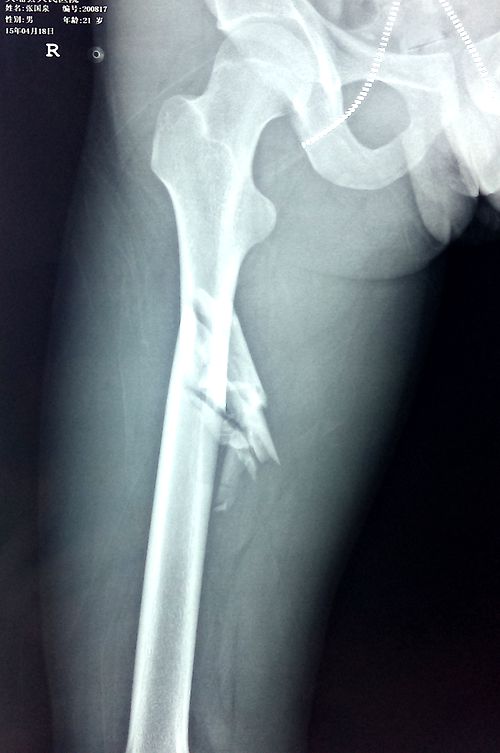

手术前

股骨股骨干骨折是基层医院骨科常见病,以往通常采取切开复位钉板系统内固定,此手术方法切口大,切口通常需要20cm-30cm,创伤大,出血多,患者功能恢复慢、差,容易出现断钉、断板,患者容易留下切口感染、关节僵硬等并发症。